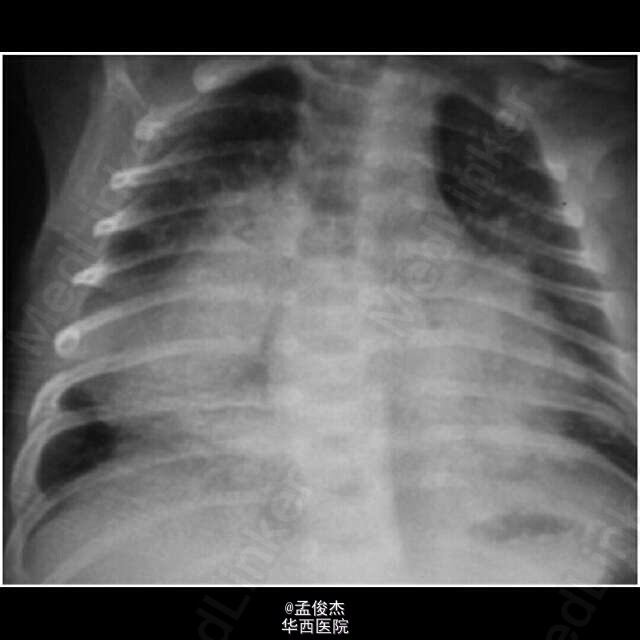

患儿母亲在2天后因为上腹痛和胸骨后痛入院。体温最高40℃,呼吸音减弱。平片显示如图1,痰液抗酸染色为阴性。使用氨苄西林和庆大霉素治疗无效,患者开始意识不清。换用抗结核药物15天后出院,2天后再次因为呼吸困难入院,HIV检测阴性,粪便和尿液抗酸染色阴性,痰培养TB阳性,继续抗结核治疗。

与此同时,婴儿出现咳嗽发热呼吸困难,出生第40天入院,呼吸64次/分,肝脾肿大(肝下6cm)。平片显示双侧肺片状影,心包轮廓模糊。脑脊液分析显示淋巴细胞增多(39% 单核, 61%中性粒),蛋白增多,葡萄糖正常,抗酸醇细菌阴性,但是在尿液粪便胃液中呈阳性。给予抗结核治疗后,肠胃胀气明显,腹部超声示腹水和膨胀的肠襻,取胃液做药敏试验。9天后患儿出现耳道脓性分泌物,抗酸醇细菌阳性,患儿气喘逐渐加重,氧饱和度84%。给予万古霉素和美罗培南治疗,患儿在2个月2天时死亡,死亡当天药敏试验报告示对异烟肼和利福平耐药。